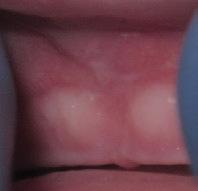

www.smilewonders.com

EDUCATION: Harvard School of Dental Medicine

EXPERTISE: Dr. Jaju is the only pediatric dentist in the MidAtlantic region who has achieved Advanced Laser Proficiency Certification from the Academy of Laser Dentistry and Breastfeeding Specialist Certification.

“During National Children’s Dental Health Month, and every month throughout the year, we want to stress the importance of taking care of your children’s teeth and oral health from the very beginning,” said Dr. Rishita Jaju, owner of Smile Wonders in Reston, Virginia and a board certified

pediatric dentist. “This helps develop healthy habits young so your children will become healthy adults.”

While we won’t say no to all sugars, there are things we can do to help prevent the negatives effects of sugar on young teeth.

1. Brush and Floss Regularly

Brush your child’s teeth or have them brush twice a day with a fluoride toothpaste and a soft-bristled brush. Wait 30-60 minutes after eating sugar or acidic foods before brushing though; brushing too soon can erode softened enamel. Always have your children brush before going to bed because as we sleep our mouths are drier, and there is a risk they won’t make enough saliva to counteract the bacteria caused by sugar left in the mouth. Clean between the teeth daily with regularly flossing. For babies, wipe your child’s gums after each meal.

2. Rinse the Mouth

When you eat, the pH level in your mouth becomes more acidic, which is never good for tooth enamel. The acid can dissolve the minerals that make up the tooth enamel and leave areas vulnerable for bacteria. After eating sugary foods, have your child rinse out or swish their mouth with plain water to counteract the plaque acids.

3. Reduce Snacking

Limit your child’s snacking on sugary foods to short periods of time, rather than snacking throughout the day. This helps reduce acid production in the mouth and lets the saliva levels rebalance in between meals.

4. Eat Healthy Foods

Feed your children healthy foods and limit sugary beverages served with meals and in-between. Vegetables and fruits are important, along with good sources of calcium like milk, yoghurt and broccoli.

5. Get Regular Dental Checkups and Cleanings

Bring your children to their pediatric dentist for regular check-ups and professional cleanings at least twice a year. This will help remove plaque and tartar that just can’t be reached with brushing and flossing.

At Smile Wonders, we prioritize preventive care by creating positive experiences for children and informative visits for parents. Come find out why kids love us and parents trust us for their infants, toddlers and children with various levels of needs and abilities.

Dr.

571-350-3663

11790 Sunrise Valley Drive, Suite 105 Reston, VA 20191

Dr. Rishita Jaju was honored to be selected as a TedX speaker in November, 2023.